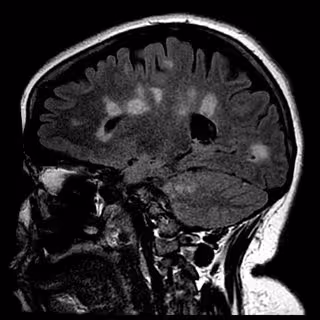

Cicatrización del cerebro en la esclerosis múltiple

Cicatrización del cerebro en la esclerosis múltiple - UNIVERSITY OF BRITISH COLUMBIA - Archivo